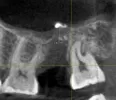

Я лечил 27-й зуб в 2016 году. Мне запломбировали каналы пастой РФ, которая вышла за пределы каналов. Сейчас в 2019 материал частично прорезался в гайморову пазуху, частично в синусе. В 2019 году удалил тот самый 27-й зуб, хочу ставить имплант, но требуется открытый синус лифтинг.

Можно проводить открытый синус лифтинг, если в синусе сидит кусочек пломбировочного материала? Чревато ли это осложнениями?

Прикрепленые фото